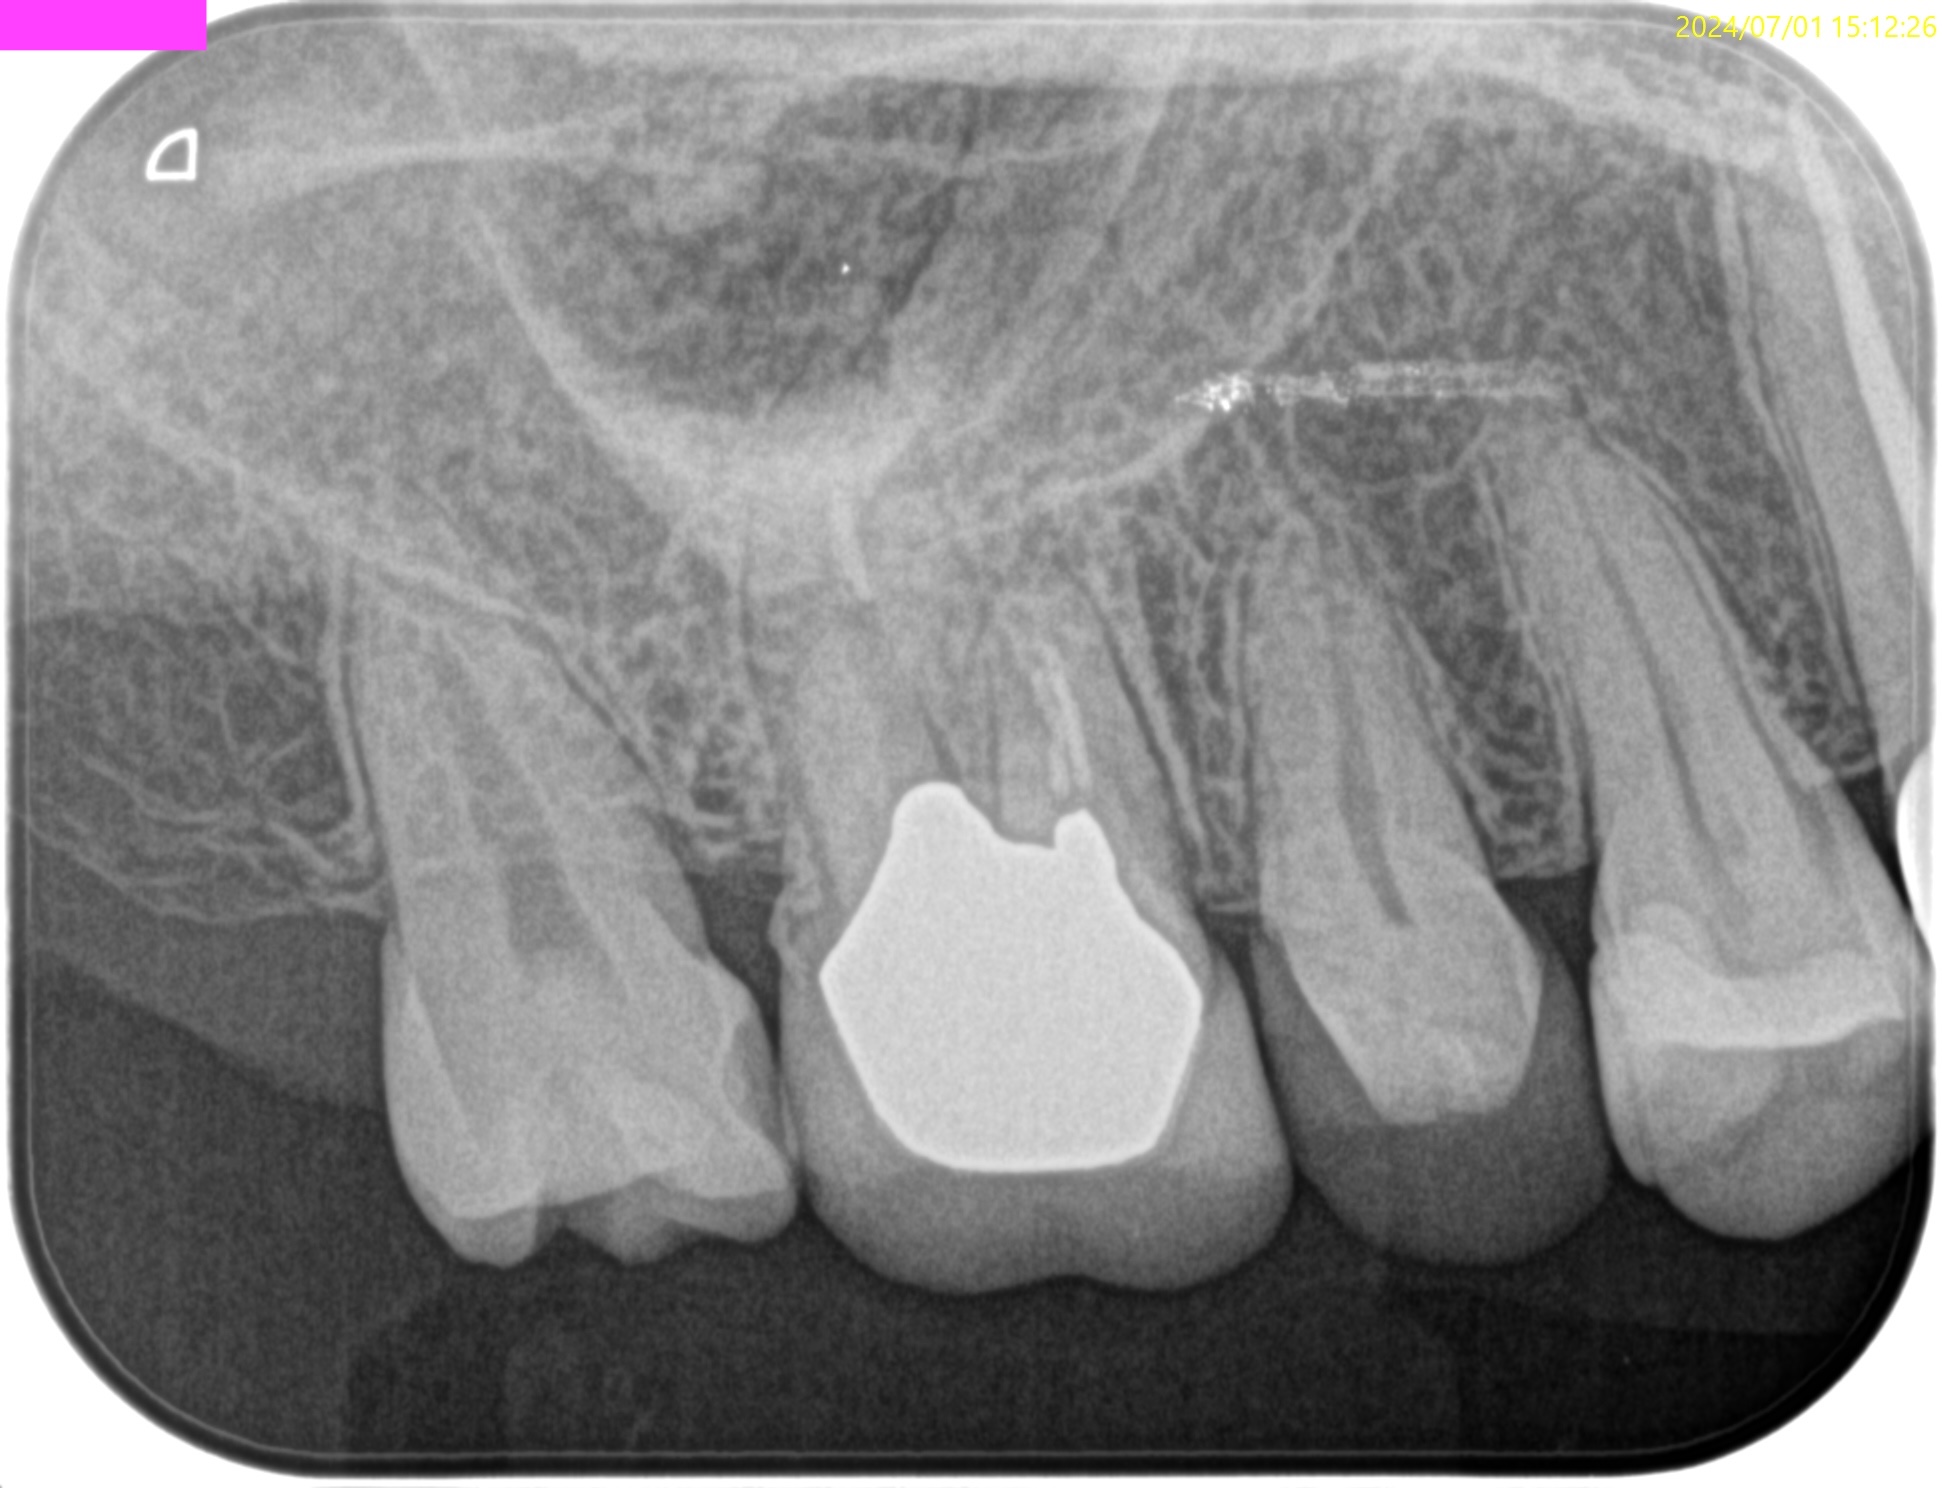

#3,14,16 Re-RCT 1yr recall(2025.10.20)

#3

MB

DB

P

#14

#16

初診時+治療直後と比較した。

劇的に病気が治癒している。

特に#16は凄まじい。

超音波洗浄しかできなかったのに根尖病変が治癒しているのだ。

免疫力が非常に強い患者さんなのだろう。